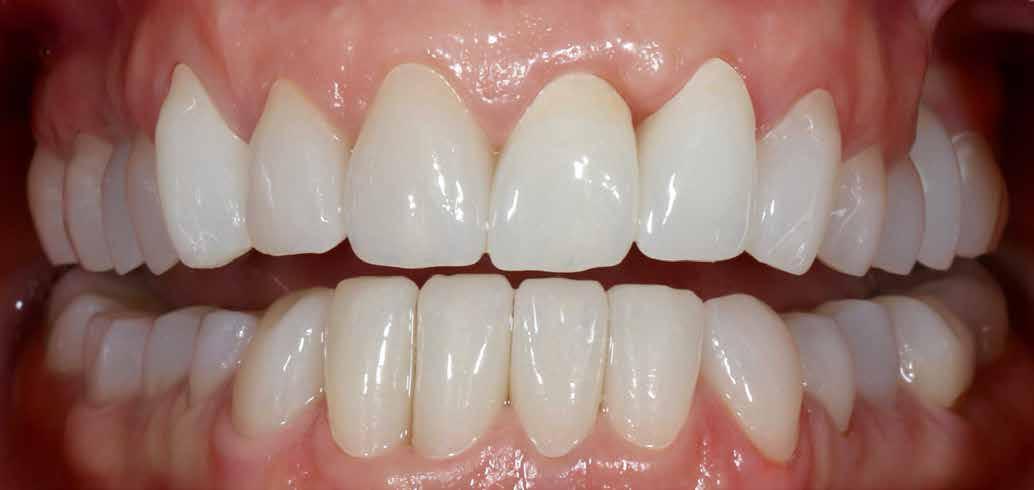

Dr. Miguel Stanley, dr. Ana Gomes Paz, dr. Inês Miguel (Portugália) Dr. Christian Coachman (Brazília) 1. ábra: Kiindulási állapot (frontális irányból). 2. ábra: A kiindulási állapotról okkluzális irányból készített felvétel (felső állcsont). 3. ábra: A kiindulási állapotról okkluzális irányból készített felvétel (alsó állcsont). 4. ábra: A kiindulási állapotról készült panorámaröntgen felvétel (2015).

2015-ben egy 47 éves férfi páciens állkapocs-ízületi panaszai miatt kereste fel a rendelőnket. Ezen felül esztétikai problémát jelentett számára, hogy az egyik felső nagymetszőfogán lévő héj eltört (1-3. ábrák). A klinikai és radiológiai vizsgálatot követően megállapítható volt, hogy a páciens kifejezett bruxizmusa miatt csökkent a harapási magassága, és jelentős mennyiségű saját foganyagot abradált el (4. ábra)

Szájterpesz használata mellett digitálisan intraorális fotók készültek a páciensről mind frontális, mind laterális és okkluzális irányokból. További fotók is készültek a páciensről egy digitális tükörreflexes kamera segítségével (frontális és laterális irányból, valamint 45 o-os szögből). Mindkét állcsontról digitális lenyomat készült egy intraorális szkenner segítségével (Care stream 3500). A maximális-interkuszpidációs helyzetet (IKP) szintén a Carestream 3500-as készülék felhasználásával rögzítet -